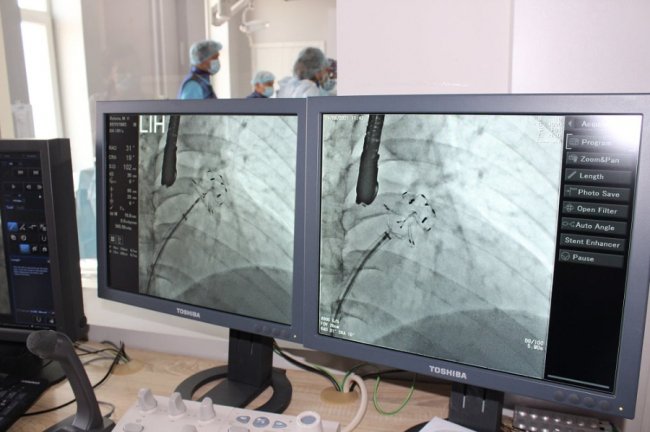

Пацієнтам імплантовано спеціальний пристрій - оклюдер останнього покоління UltraSept LAA виробництва CARDIA (USA).

Обидві операції пройшли успішно. Їх проводили за допомогою ангіографа (із застосуванням рентгенологічного обладнання) через прокол у судині на нозі і не потребували хірургічних розрізів.